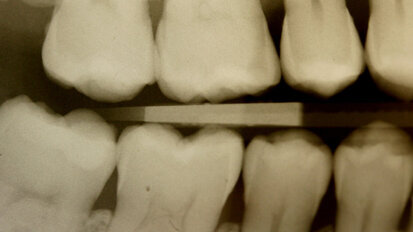

Rehabilitace Straumann